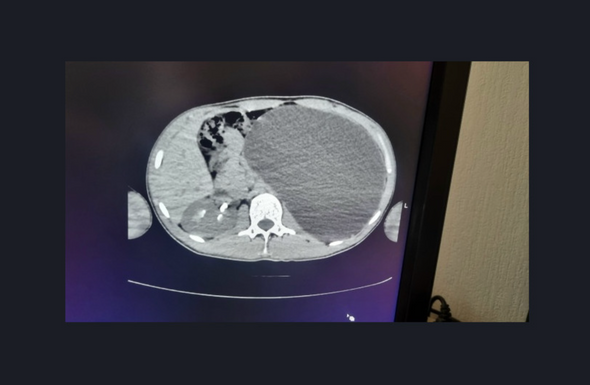

«Это была случайная находка. Парень к нам поступил из амбулаторного звена. Он устраивался на работу. Ему перед трудоустройством сделали УЗИ, нашли объемное образование в брюшной полости. Мы стали обследовать, оказалось, что это гидронефроз левой почки с отсутствием паренхимы (основная ткань органа, выполняющая его функции). У нашего пациента почка достигла размеров пятилитровой бутылки! Она занимала почти весь объем живота и давила на все соседние органы. Это была настоящая „бомба замедленного действия“: любая травма, случайный удар в живот — и мешок мог разорваться внутри», — рассказала детский хирург-уролог Ирина Живолуп.

Гидронефроз — это заболевание почки, которое характеризуется стойким нарастающим расширением ее полостей, атрофией почечной паренхимы в результате нарушения циркуляции крови и оттока мочи из почки. Эта патология приводит к повышению внутрилоханочного давления и повреждению почечной ткани. Часто гидронефроз длительное время протекает бессимптомно и обнаруживается случайно при УЗИ.

Во время операции хирургам пришлось фактически доставать «пятилитровую бутылку» через «замочную скважину». Через четыре небольших прокола они откачали всю скопившуюся в почке жидкость, а затем удалили орган. Сейчас пациент идет на поправку.